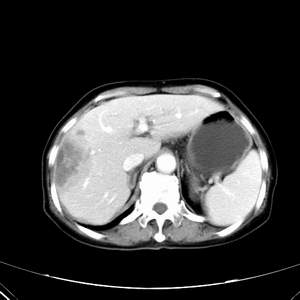

患者,女性,77岁,右上腹胀痛月余。afp正常。ca125升高。即往无肝炎病史。

肝右叶病灶是胆管细胞癌吗?门静脉右支癌栓形成?右侧肾上腺有问题吗?

病灶强化不均匀,形态欠规整.患者年龄很高.

考虑肝癌

肾上腺应该问题不大,肾上腺的大小和形态在临床上差异很大,所以大小无实际意义

病灶渐进性向心性强化,延时病灶中心见条片状高密度影,局部见肝包膜回缩征,结合病人无肝炎病史,考虑肝右叶胆管细胞癌,门脉右支癌栓形成。